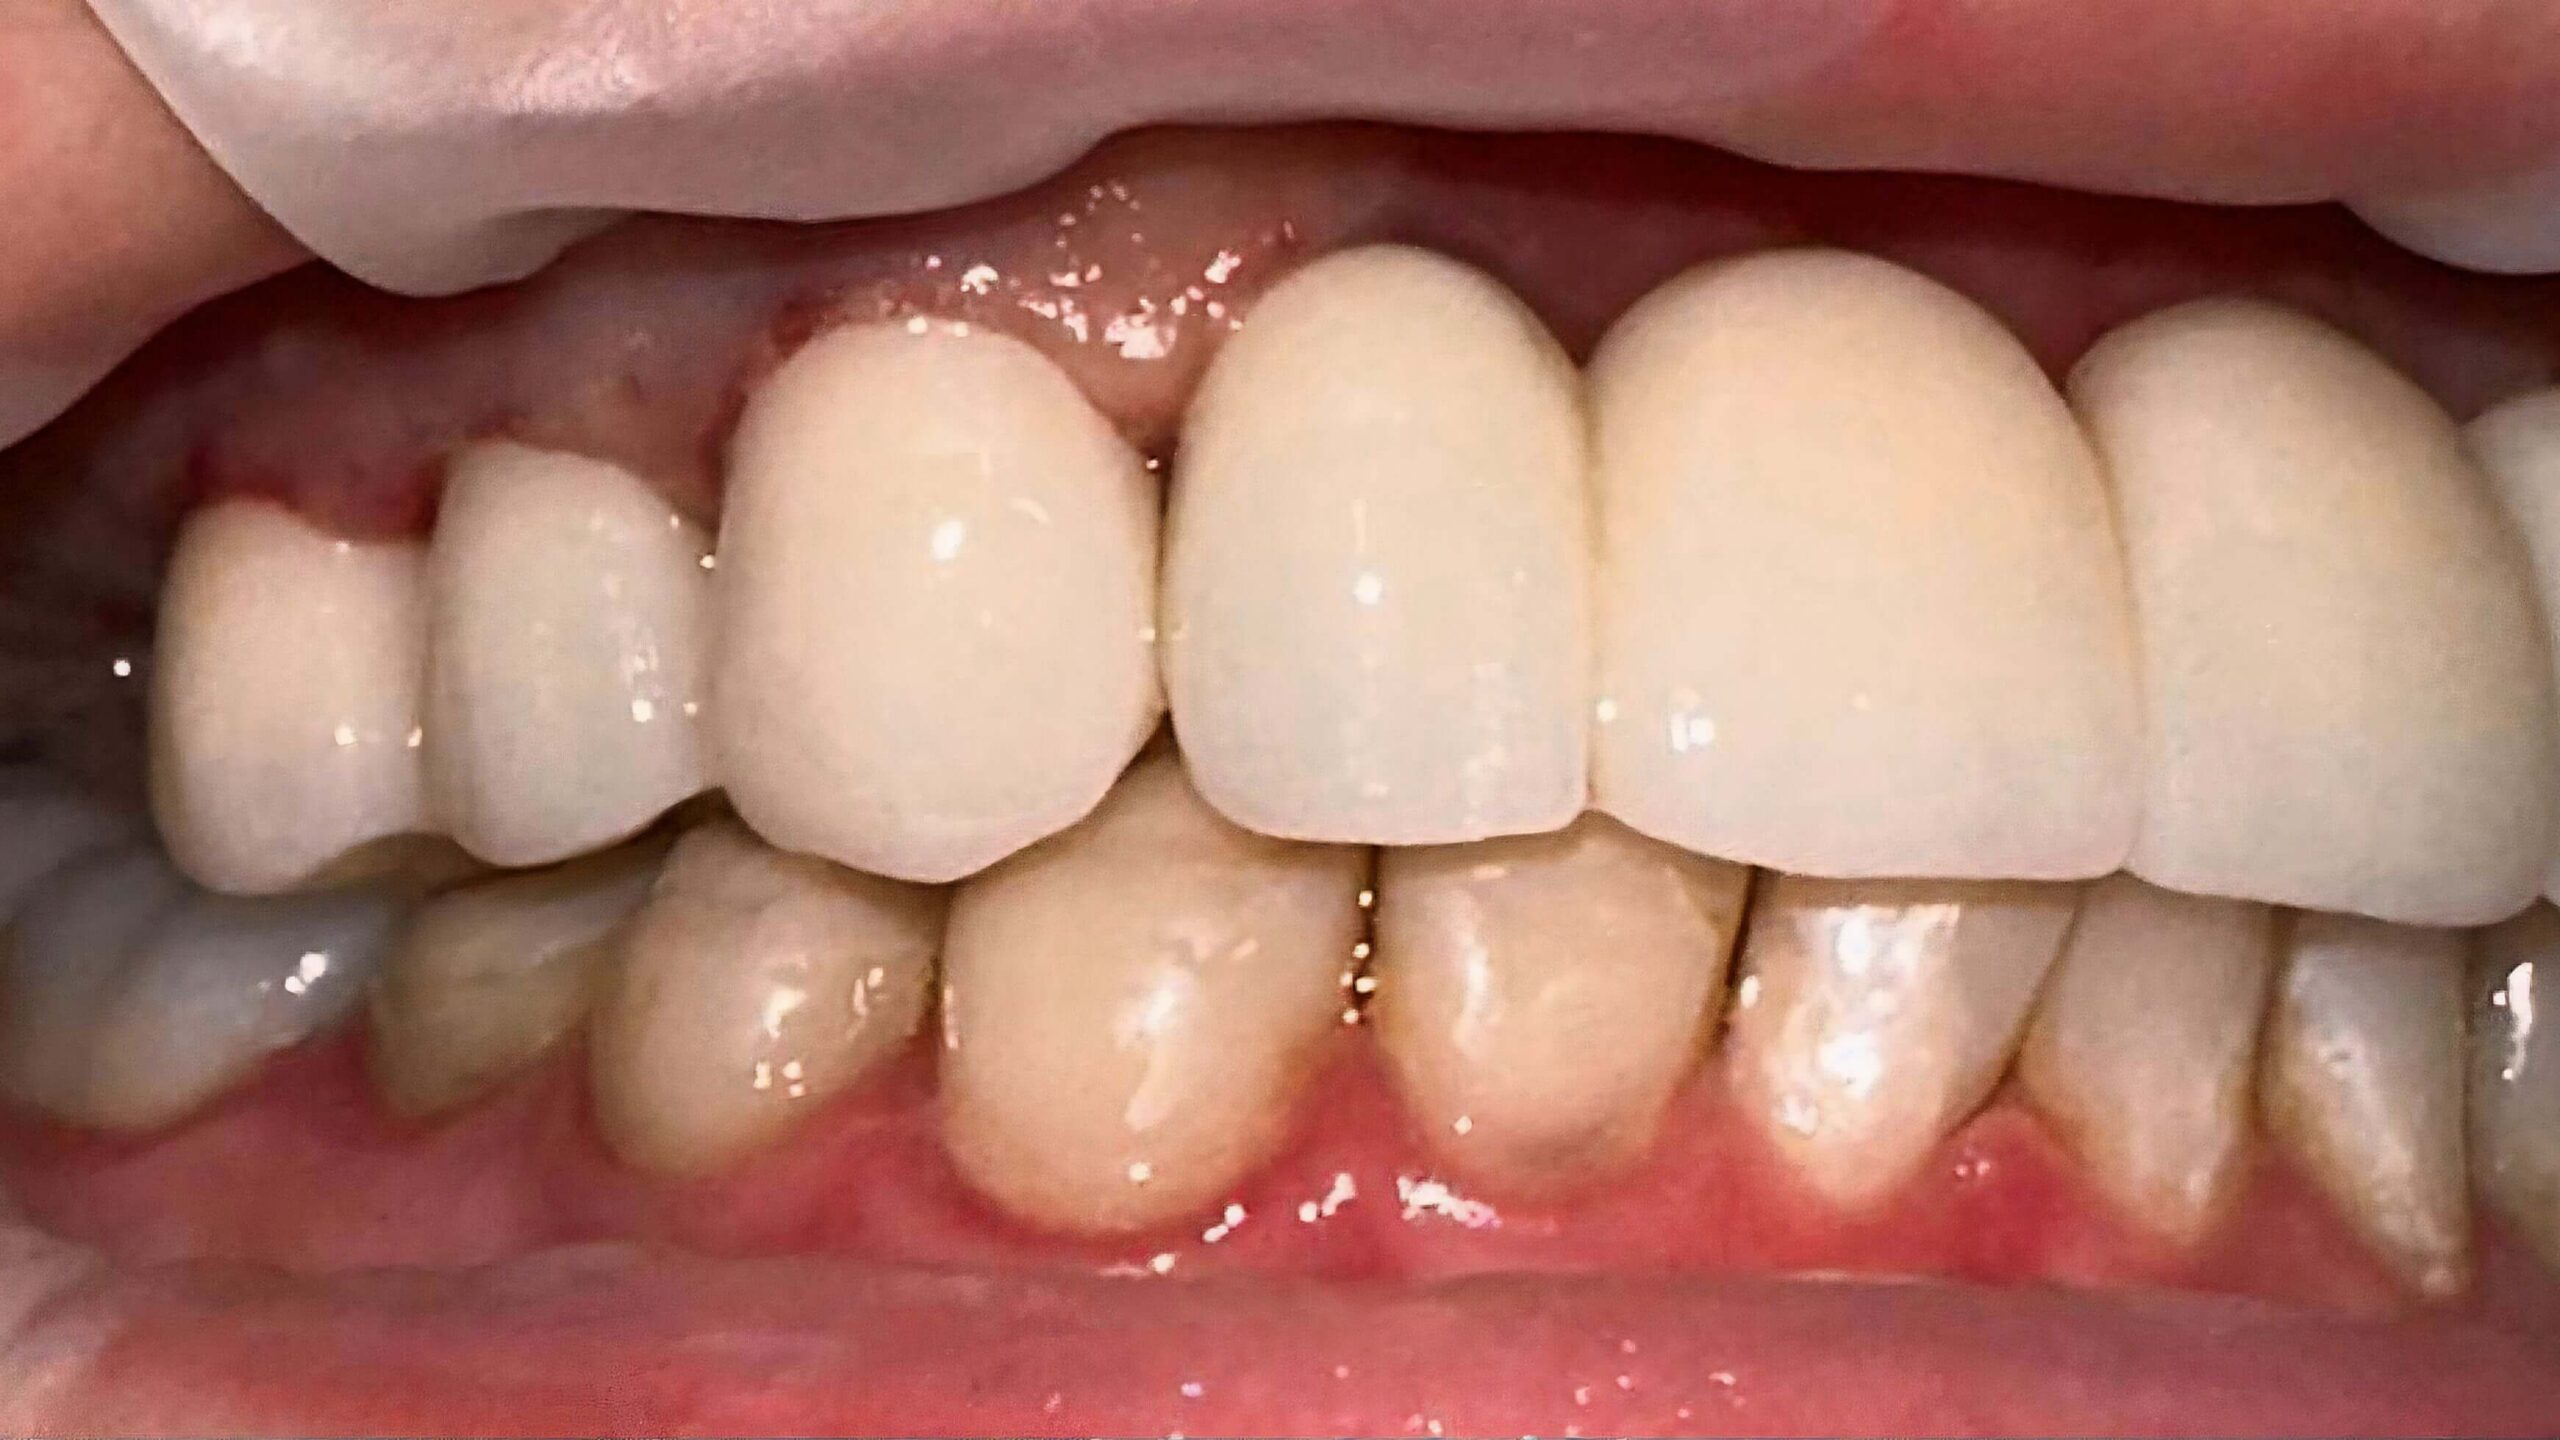

Протезування передніх зубів

Вихідна ситуація: потемніння передніх зубів, відсутність деяких зубів на верхній щелепі, що ускладнювало процес жування. Оцінивши стан залишкових зубів та ясен запропонували протезування передніх зубів. У результаті пацієнт отримав повністю відновлені передні зуби, які виглядають та функціонують як натуральні, що покращило його зовнішній вигляд та повернуло впевненість у собі й комфорт у спілкуванні.